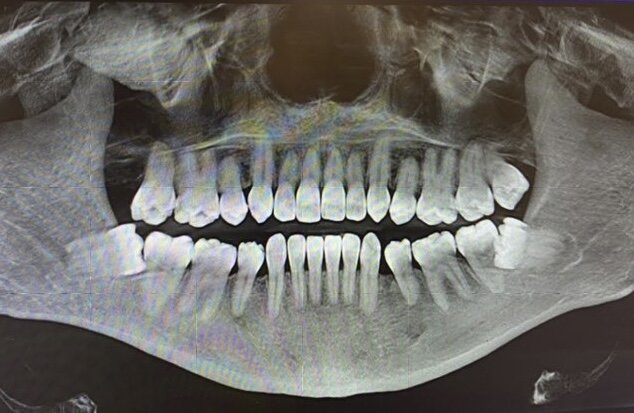

Покажу фото такого клинического случая.

Зубы мудрости таранят корни соседних 7-к

Смотрите, у 7-ки слева корень рассосался. А вот 8-ка справа растет примерно так же, но по этому снимку нельзя оценить рассосался ли корень правой 7-ки, либо просто накладывается проекция зуба на зуб. Чтобы ответить на 100% точно по поводу правой стороны, нужно КТ. Разберемся с этим. А слева всё очевидно, поезд ушел.